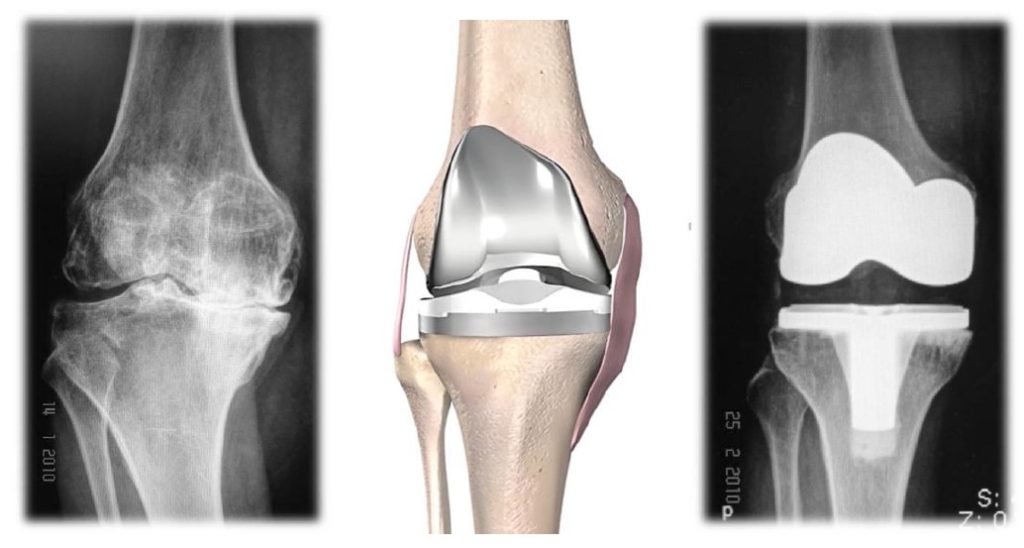

การผ่าตัดเปลี่ยนข้อเข่าเทียมคืออะไร

คือการผ่าตัดเพื่อนผิวข้อเข่าเดิมที่เสื่อมสภาพออก และทดแทนผิวข้อใหม่ด้วยข้อเข่า เทียม

ข้อเข่าเทียมทําจากอะไร

ข้อเข่าเทียมมีส่วนประกอบสําคัญ 4 ส่วน ได้แก่

- ส่วนผิวกระดูกต้นขา (Femoral component) ทําจากโลหะผสมกลุ่มโครบอลท์และโครเมียม มีลักษณะผิวเรียบ มีรูปร่างและทําหน้าที่เหมือนกระดูกอ่อนผิวข้อของกระดูกต้นขา

- ส่วนผิวกระดูกแข้ง (Tibial component) ทําจากโลหะผสมกลุ่มไทเทเนียม มีลักษณะเป็นแป้นสําหรับวางบนกระดูกแข้ง

- ส่วนหมอนรองข้อเทียม (Polyethylene) เป็นพลาสติกชนิดพิเศษอยู่ตรงกลางระหว่างโลหะทั้งสองชิ้น ทําหน้าที่รับและกระจายน้ำหนัก

- ส่วนผิวกระดูกสะบ้า (Patellar component) เป็นพลาสติกชนิดพิเศษรูปร่างคล้ายเหรียญ ทําหน้าที่ทดแทนผิวสะบ้าเดิม